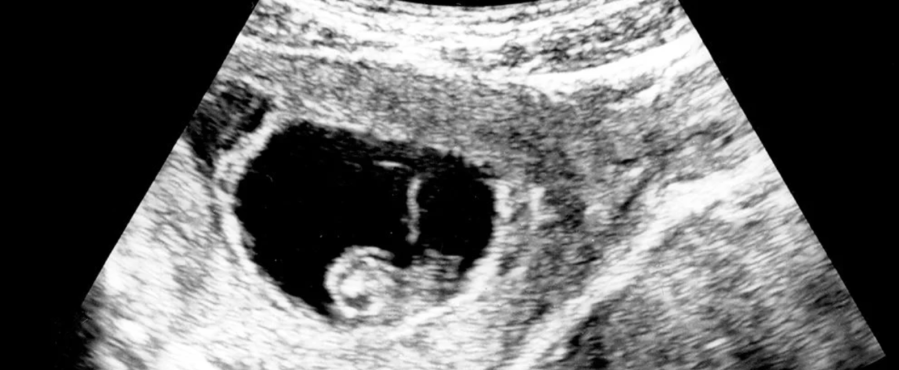

six-week-embryo-flutter